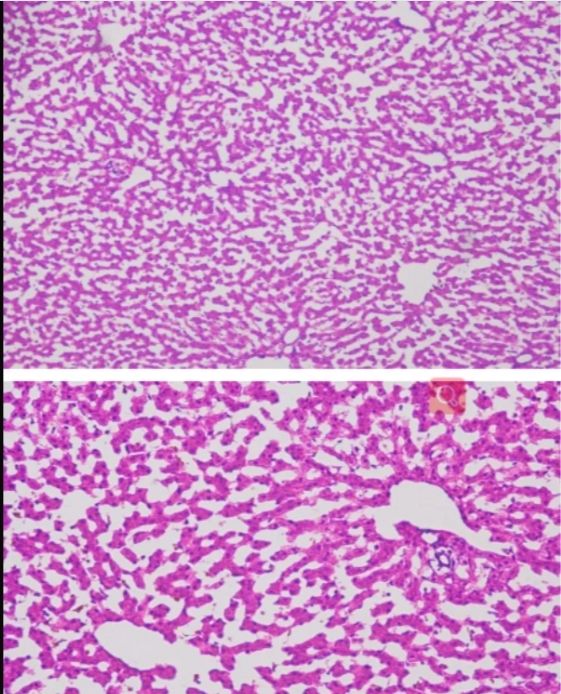

㈠觀察組織細(xì)胞的微觀結(jié)構(gòu):通過冰凍切片,研究人員可以獲得組織細(xì)胞的二維圖像,進(jìn)而觀察和分析細(xì)胞的形態(tài)、大小、排列方式等微觀結(jié)構(gòu)特征。這對(duì)于了解細(xì)胞的結(jié)構(gòu)和功能,以及揭示疾病的發(fā)病機(jī)制和病理變化具有重要意義。